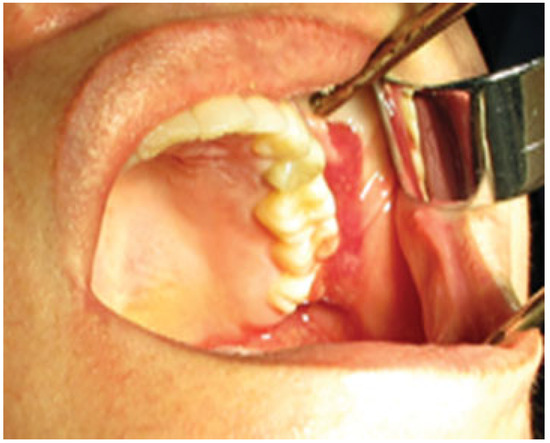

Diagnosis was put on the injection of local anesthetic solution into the gel implant site causing further expansion and discomfort. Treatment plan was given to remove the entire manipulated gel implant. This was performed through an intraoral incision under an intravenous sedation process (Figure 1). A pen-rose drain was placed at the incision site and patient was discharged after 2 days while being on an antibiotic, analgesic, and chlorhexidine mouthwash regimen for 10 days. Results of the follow-up of the case in 10, 20, and 30 days showed the reduced size of the swelling to normal gradually. Inflammation was subsided in a slow pattern, while the full recovery was achieved in 6 months with a normal facial appearance (Figure 2).

Figure 1. Intraoperative feature showing easy evacuation of facial gel.